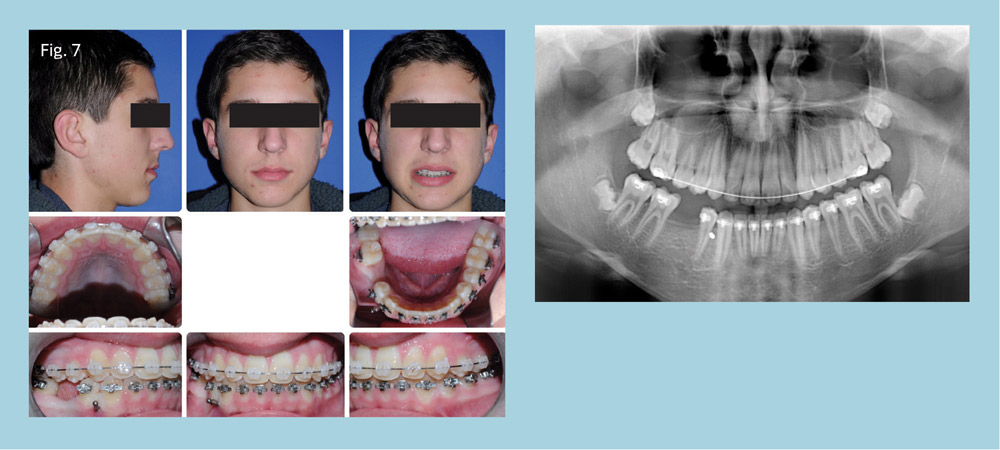

At the next appointment, an 8mm TAD was placed between teeth 27 and 28 (Fig. 7). Immediate loading of the TAD using a 6mm closed NiTi spring was utilized for direct anchorage to tooth 30.

The majority of space closure was performed on a 16x22 NiTi using sliding mechanics. The initial TAD failed after eight weeks and a new TAD was placed mesial to tooth 27, using the same anchorage protocol.